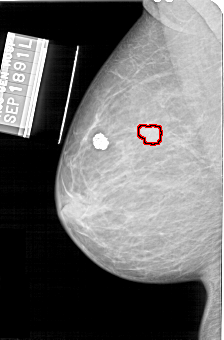

A_1568_1.LEFT_MLO

LEFT_MLO LINES 5086 PIXELS_PER_LINE 3346 BITS_PER_PIXEL 12 RESOLUTION 43.5 OVERLAY

FILE: A_1568_1.LEFT_MLO.OVERLAY

TOTAL_ABNORMALITIES 1

ABNORMALITY 1

LESION_TYPE MASS SHAPE LOBULATED MARGINS MICROLOBULATED

ASSESSMENT 4

SUBTLETY 2

PATHOLOGY BENIGN

TOTAL_OUTLINES 1

BOUNDARY